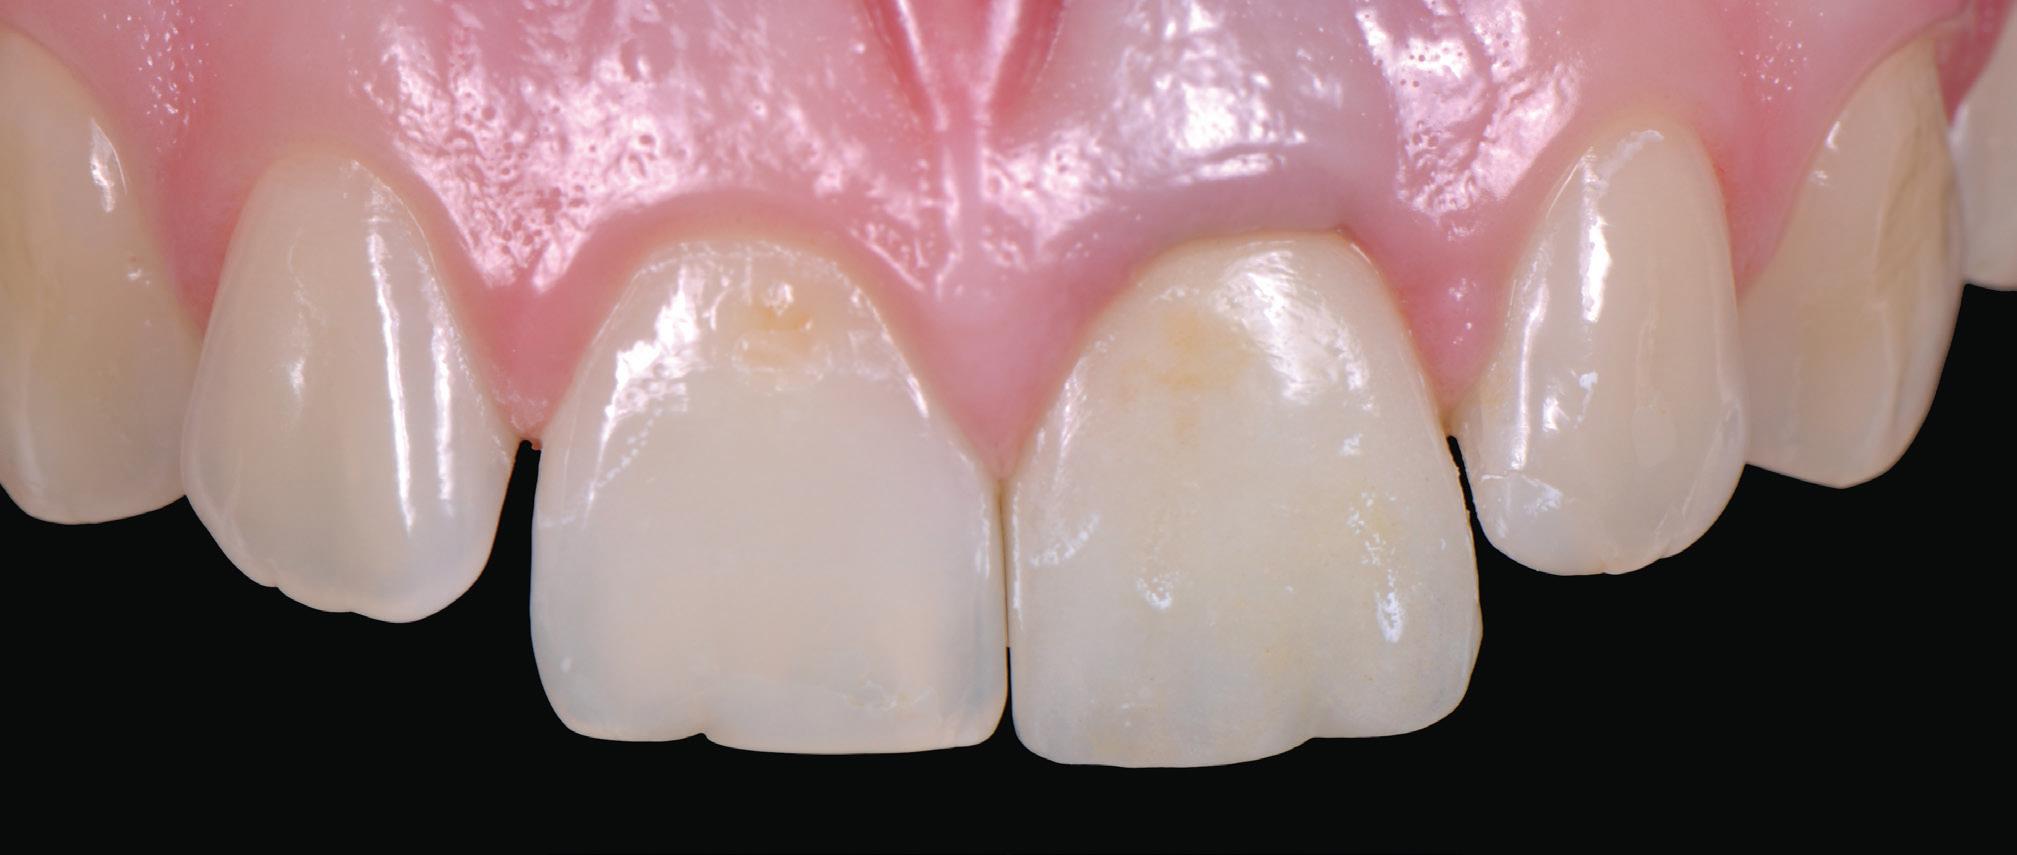

Many of the “valuation” enquiries I received were in fact requests for help with dental business problems in which case the dentist’s hidden agendas were identified and dealt with but valuation not proceeded with. 33 years of examining dental financials, including benchmarking dental practice efficiency, doing tax planning for dentists, helping dentists negotiate practice buy and sell agreements or sensitive dental associateships, gave me a rewarding insight into the Australian dental profession. I was fortunate to enjoy dental client relationships Australia-wide and to observe the differences in practice of financially very successful dentists and some who have struggled.

Knowing your own practice.